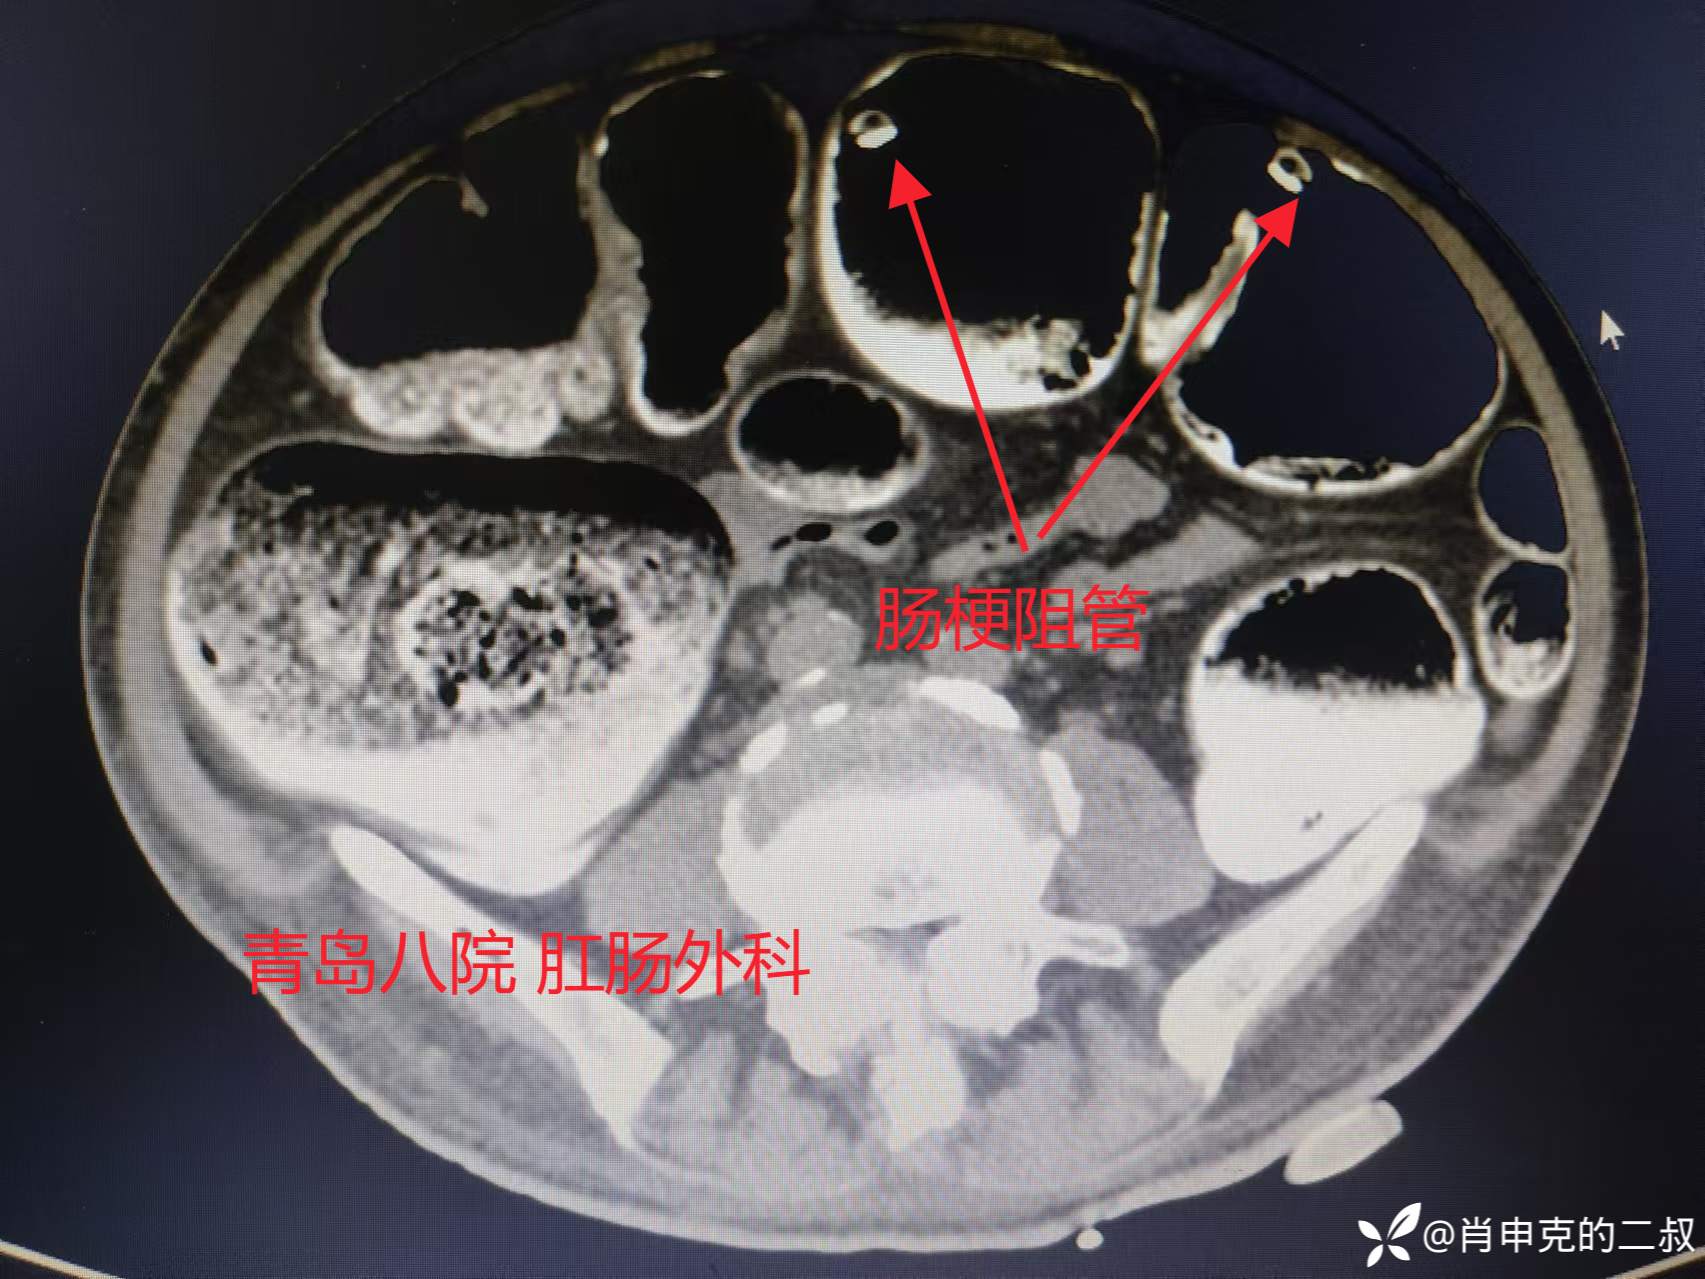

肠梗阻管治疗第3日,复查腹部CT,并无明确好转。

翌日,患者DSA下放置肠梗阻管治疗。放置过程中可见结肠内大量干粪块,肠道内完全堵塞。。不过介入医生水平可以,肠梗阻放入横结肠近端。